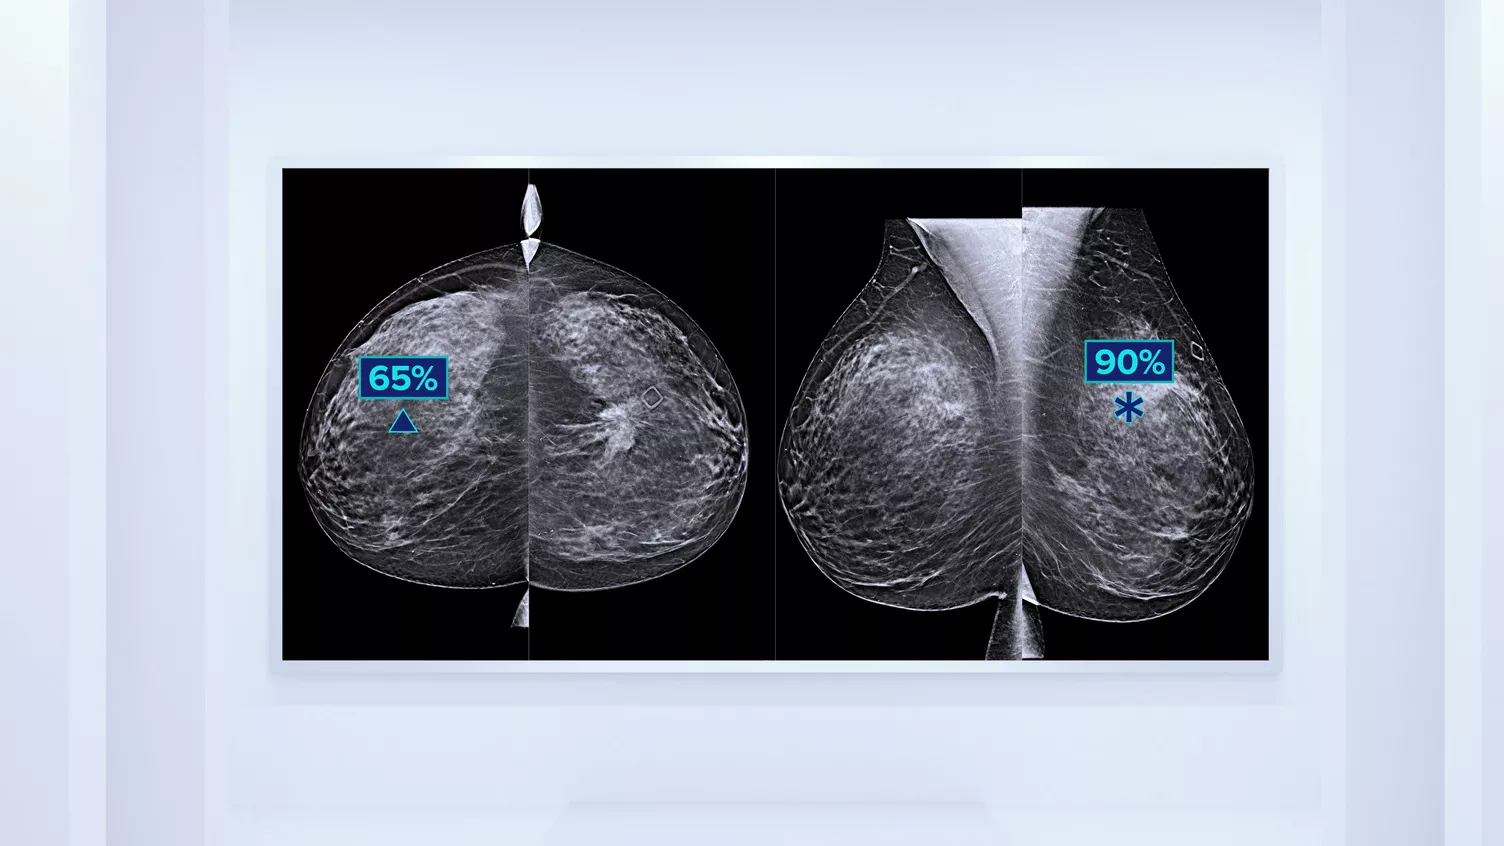

Utöver volym kan mönster och textur av fibroglandulär vävnad spela en lika viktig roll vid mammografisk riskbedömning av cancer.3–5 Genom att analysera och kategorisera bröstets textur och mönster kan vår teknik ge den exakta informationen som du behöver för att uppnå mer konsekvent och tillförlitlig bedömning samt tillförlitlig utformning av patientspecifik screening.

Objektiv maskininlärningsalgoritm som tilldelar en kategori för brösttäthet baserat på analys av bröstvävnadens textur och mönster.

* Poängbedömningar baseras på ACR BI-RADS-kategorier enligt de reviderade riktlinjerna från American College of Radiation (ACR) BI-RADS Atlas 5th Edition. Detta motsvarar mönster och textur jämfört med volym vid bedömning av täthet.